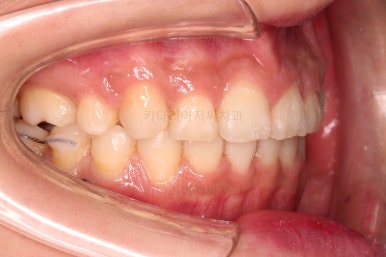

1. 초진

연산동교정치과 초진 시 입안의 모습입니다.

아랫니 어금니가 하나 없어서 주위 치아들이 해당 위치로 쓰러진 상태였습니다.

그리고 양쪽의 교합이 톱니바퀴처럼 맞물려 있는 것 같지만 톱니바퀴가 한 칸씩 밀려서 맞물려 있는 부정교합이 있는 상태였습니다.